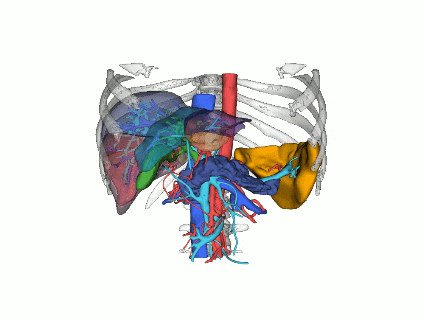

4.模拟手术过程

通过虚拟手术模拟,医师可以提前预演手术过程,评估手术难度及风险,制定应对措施,确保手术顺利进行。

5.提高手术安全性

三维重建技术能够清晰显示肝脏内的血管分布,帮助医师在手术中避开重要血管,减少出血风险。通过精确的术前规划,医师可以最大限度地保留正常肝组织,减少术后肝功能衰竭的风险。

阿梵D-三维重建后动静脉整体预览